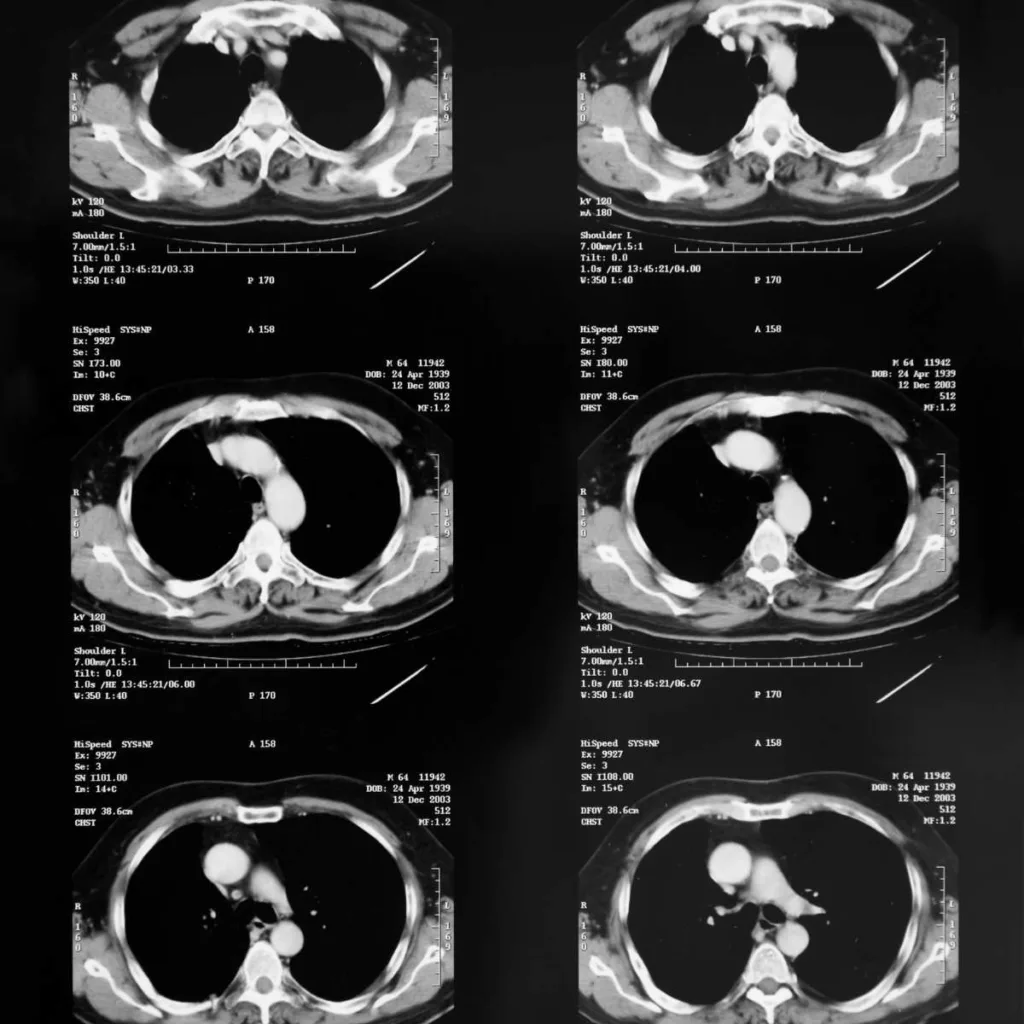

Resonancia Magnética de Tórax